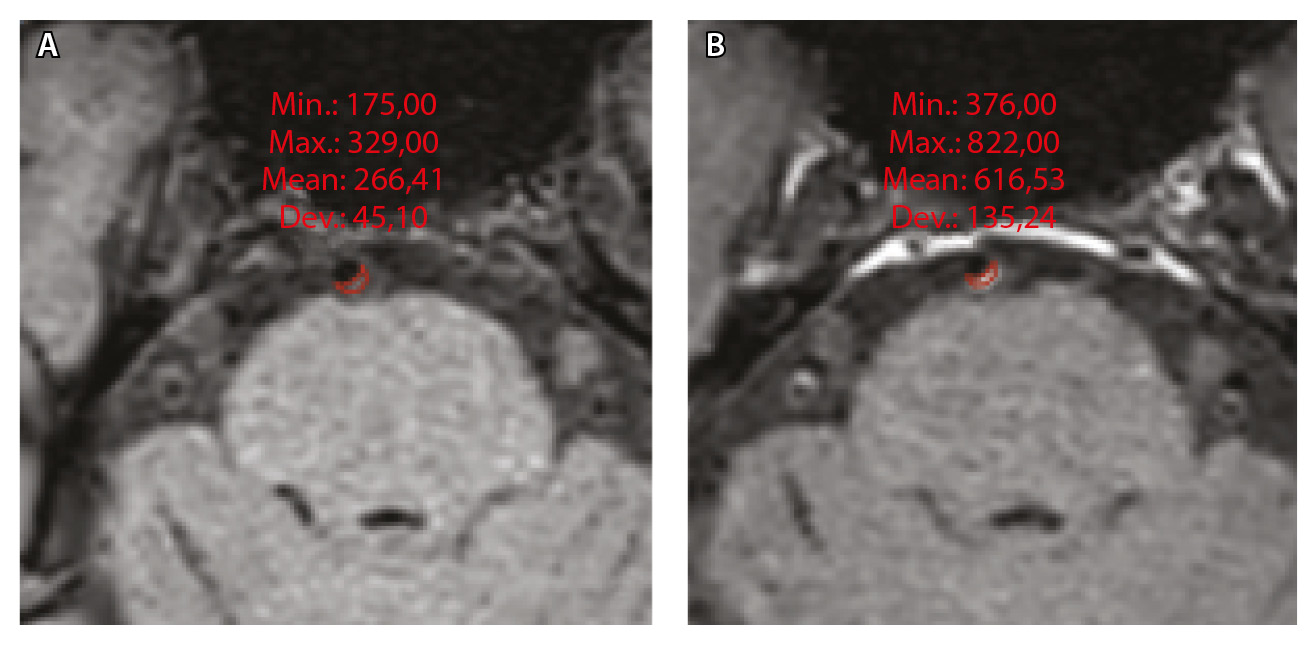

Для количественной оценки степени накопления контрастного вещества в области интереса (АСБ, неизмененная сосудистая стенка, воронка гипофиза) рассчитывали WEI по формуле:

,

где WEI (wall enhancement index) – индекс усиления контрастности стенки (сосудов), SIwallprecontrast – интенсивность сигнала (Signal Intensity, SI) сосудистой стенки (wall) в зоне интереса на преконтрастных (precontrast) изображениях, SIwallpostcontrast – интенсивность сосудистой стенки в зоне интереса на постконтрастных (postcontrast) изображениях; SIbrainprecontrast – интенсивность неизмененного белого вещества мозга (brain) на доконтрастных изображениях; SIbrainpostcontrast – интенсивность неизмененного белого вещества мозга на постконтрастных изображениях. Пример измерения интенсивности сигнала от АСБ для расчета WEI приведен на рисунке 1.

Рис. 1. Пример измерения интенсивности эхо-сигнала от атеросклеротической бляшки базилярной артерии для расчета индекса усиления контрастности стенки сосуда (WEI). В месте максимального стеноза артерии на одном срезе отмечали область интереса (ROI) и регистрировали среднее значение интенсивности сигнала от сосудистой стенки (SIwall). ROI были сопоставлены по размеру и местоположению в наборе данных T1-TSE-db-FS до (А) и после (Б) контрастного усиления; макс. – максимум, мин. – минимум, откл. – отклонение, средн. – среднее